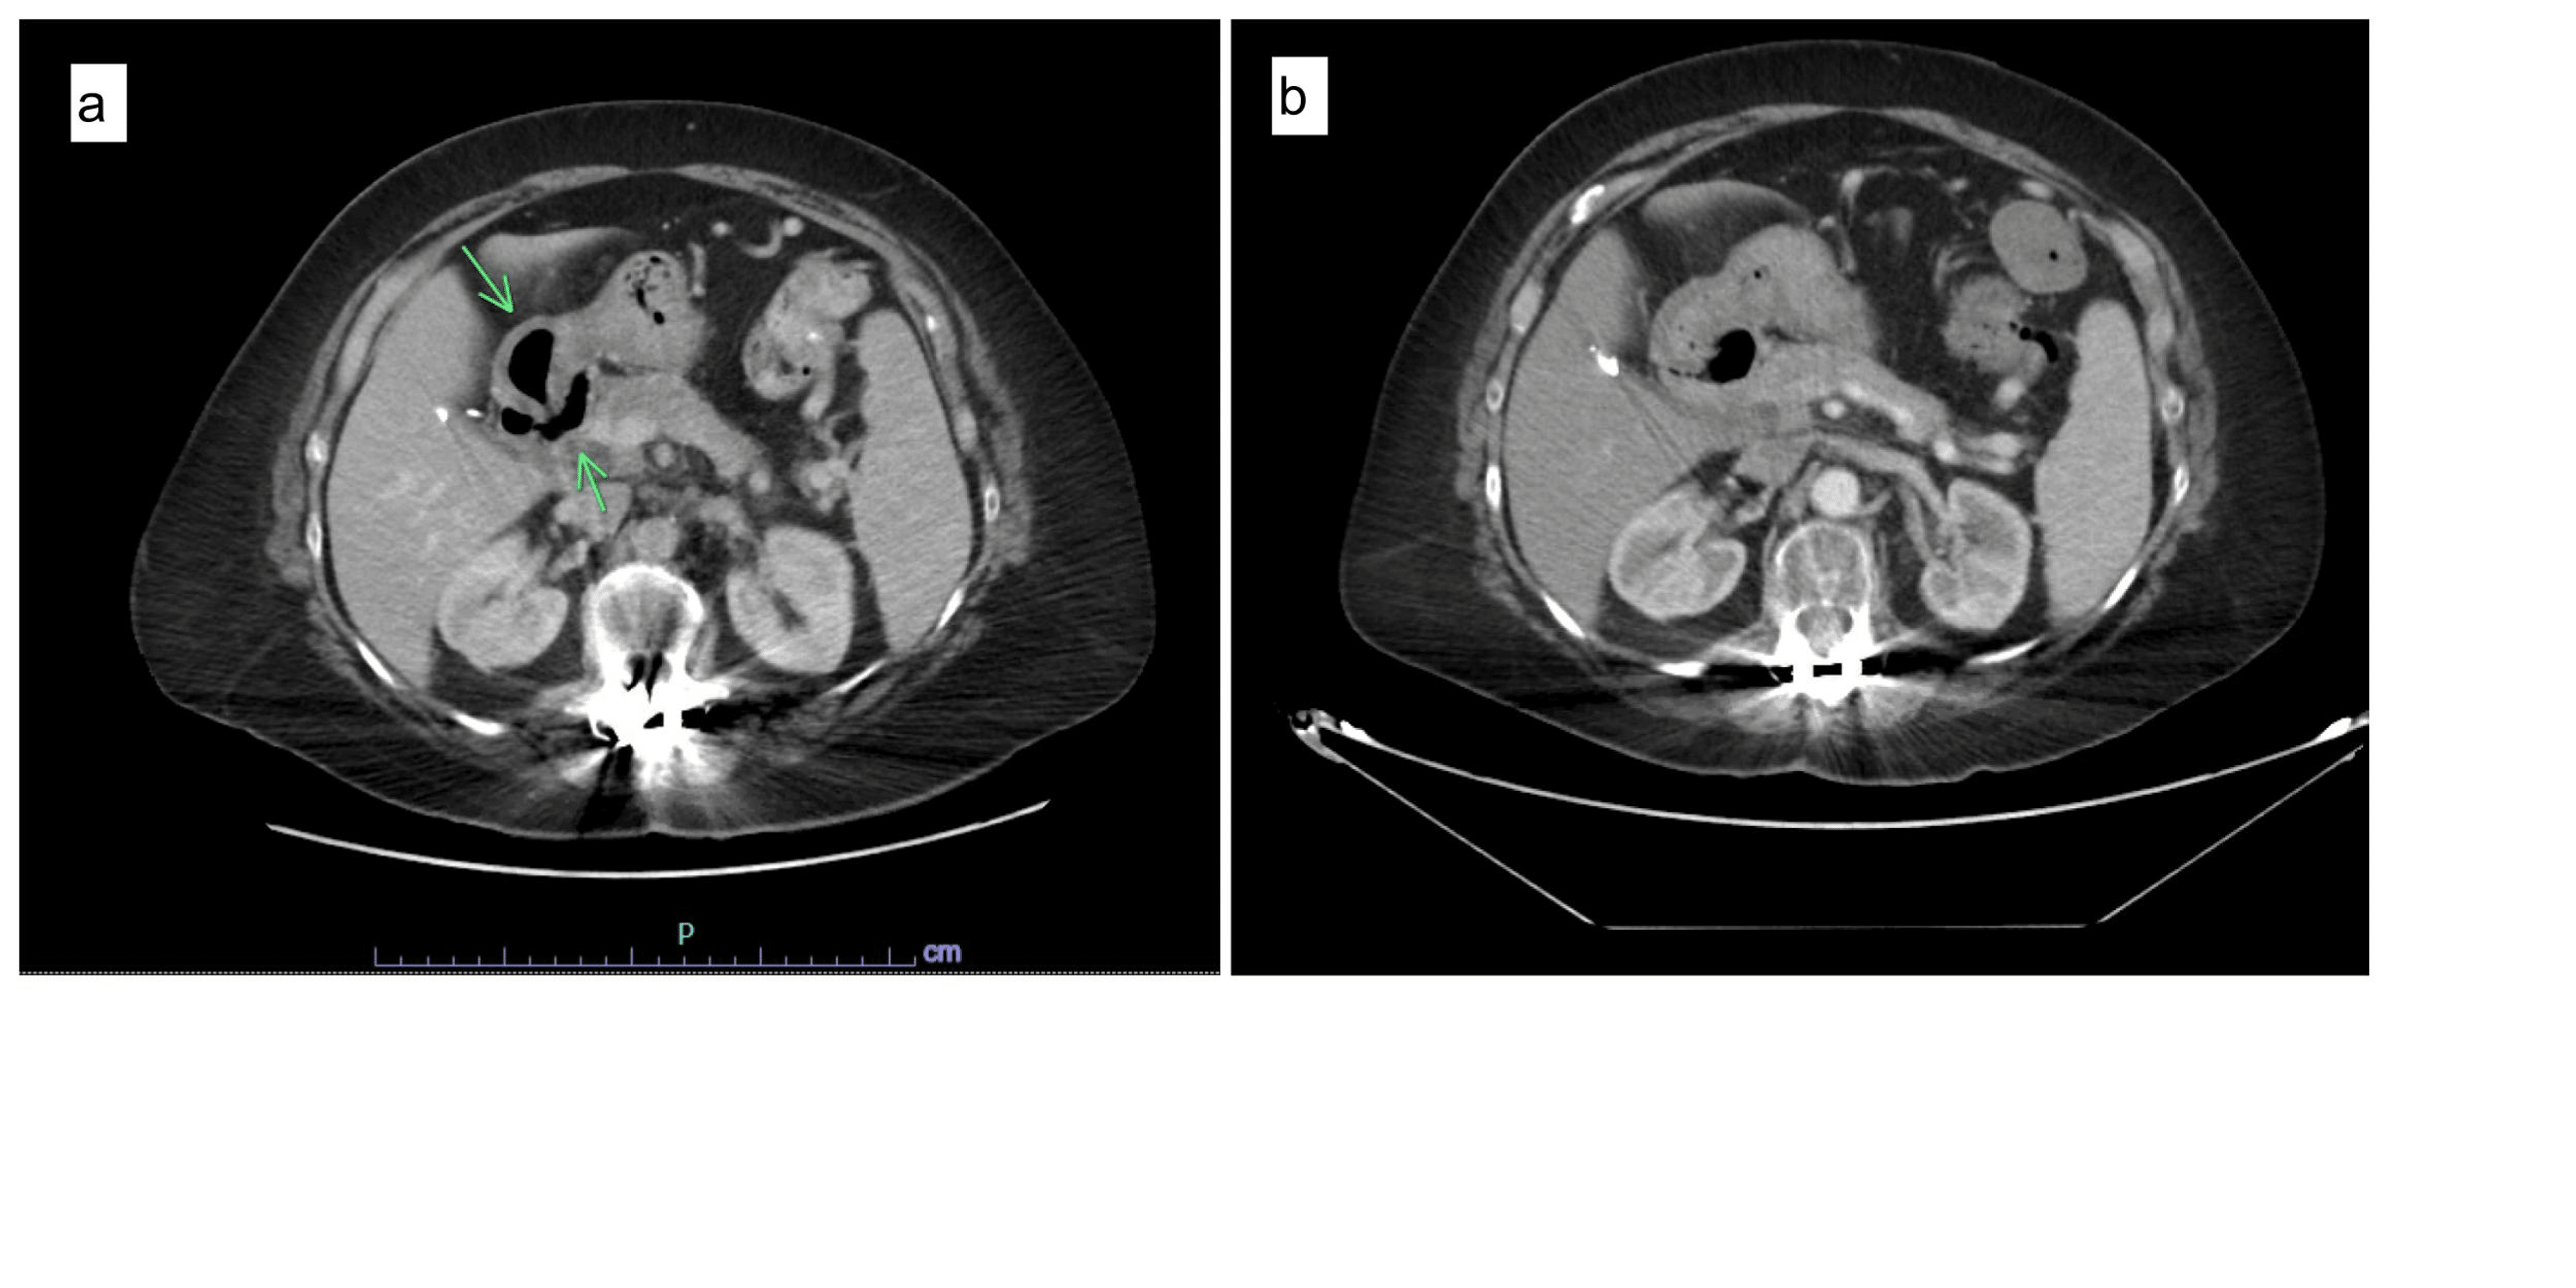

From www.researchgate.net

Apple core lesion in small bowel, see circle tomography). Download Scientific Diagram Apple-Core Lesion Colon Cause 1 abnormal bowel wall changes on. the apple core sign, also known as the napkin ring sign (bowel), is most frequently associated with. “apple core lesions” on abdominal imaging are commonly associated with malignancy constricting the colonic lumen. we present a case of cic due to extensive atherosclerotic disease of the superior mesenteric artery (sma), which presented. Apple-Core Lesion Colon Cause.